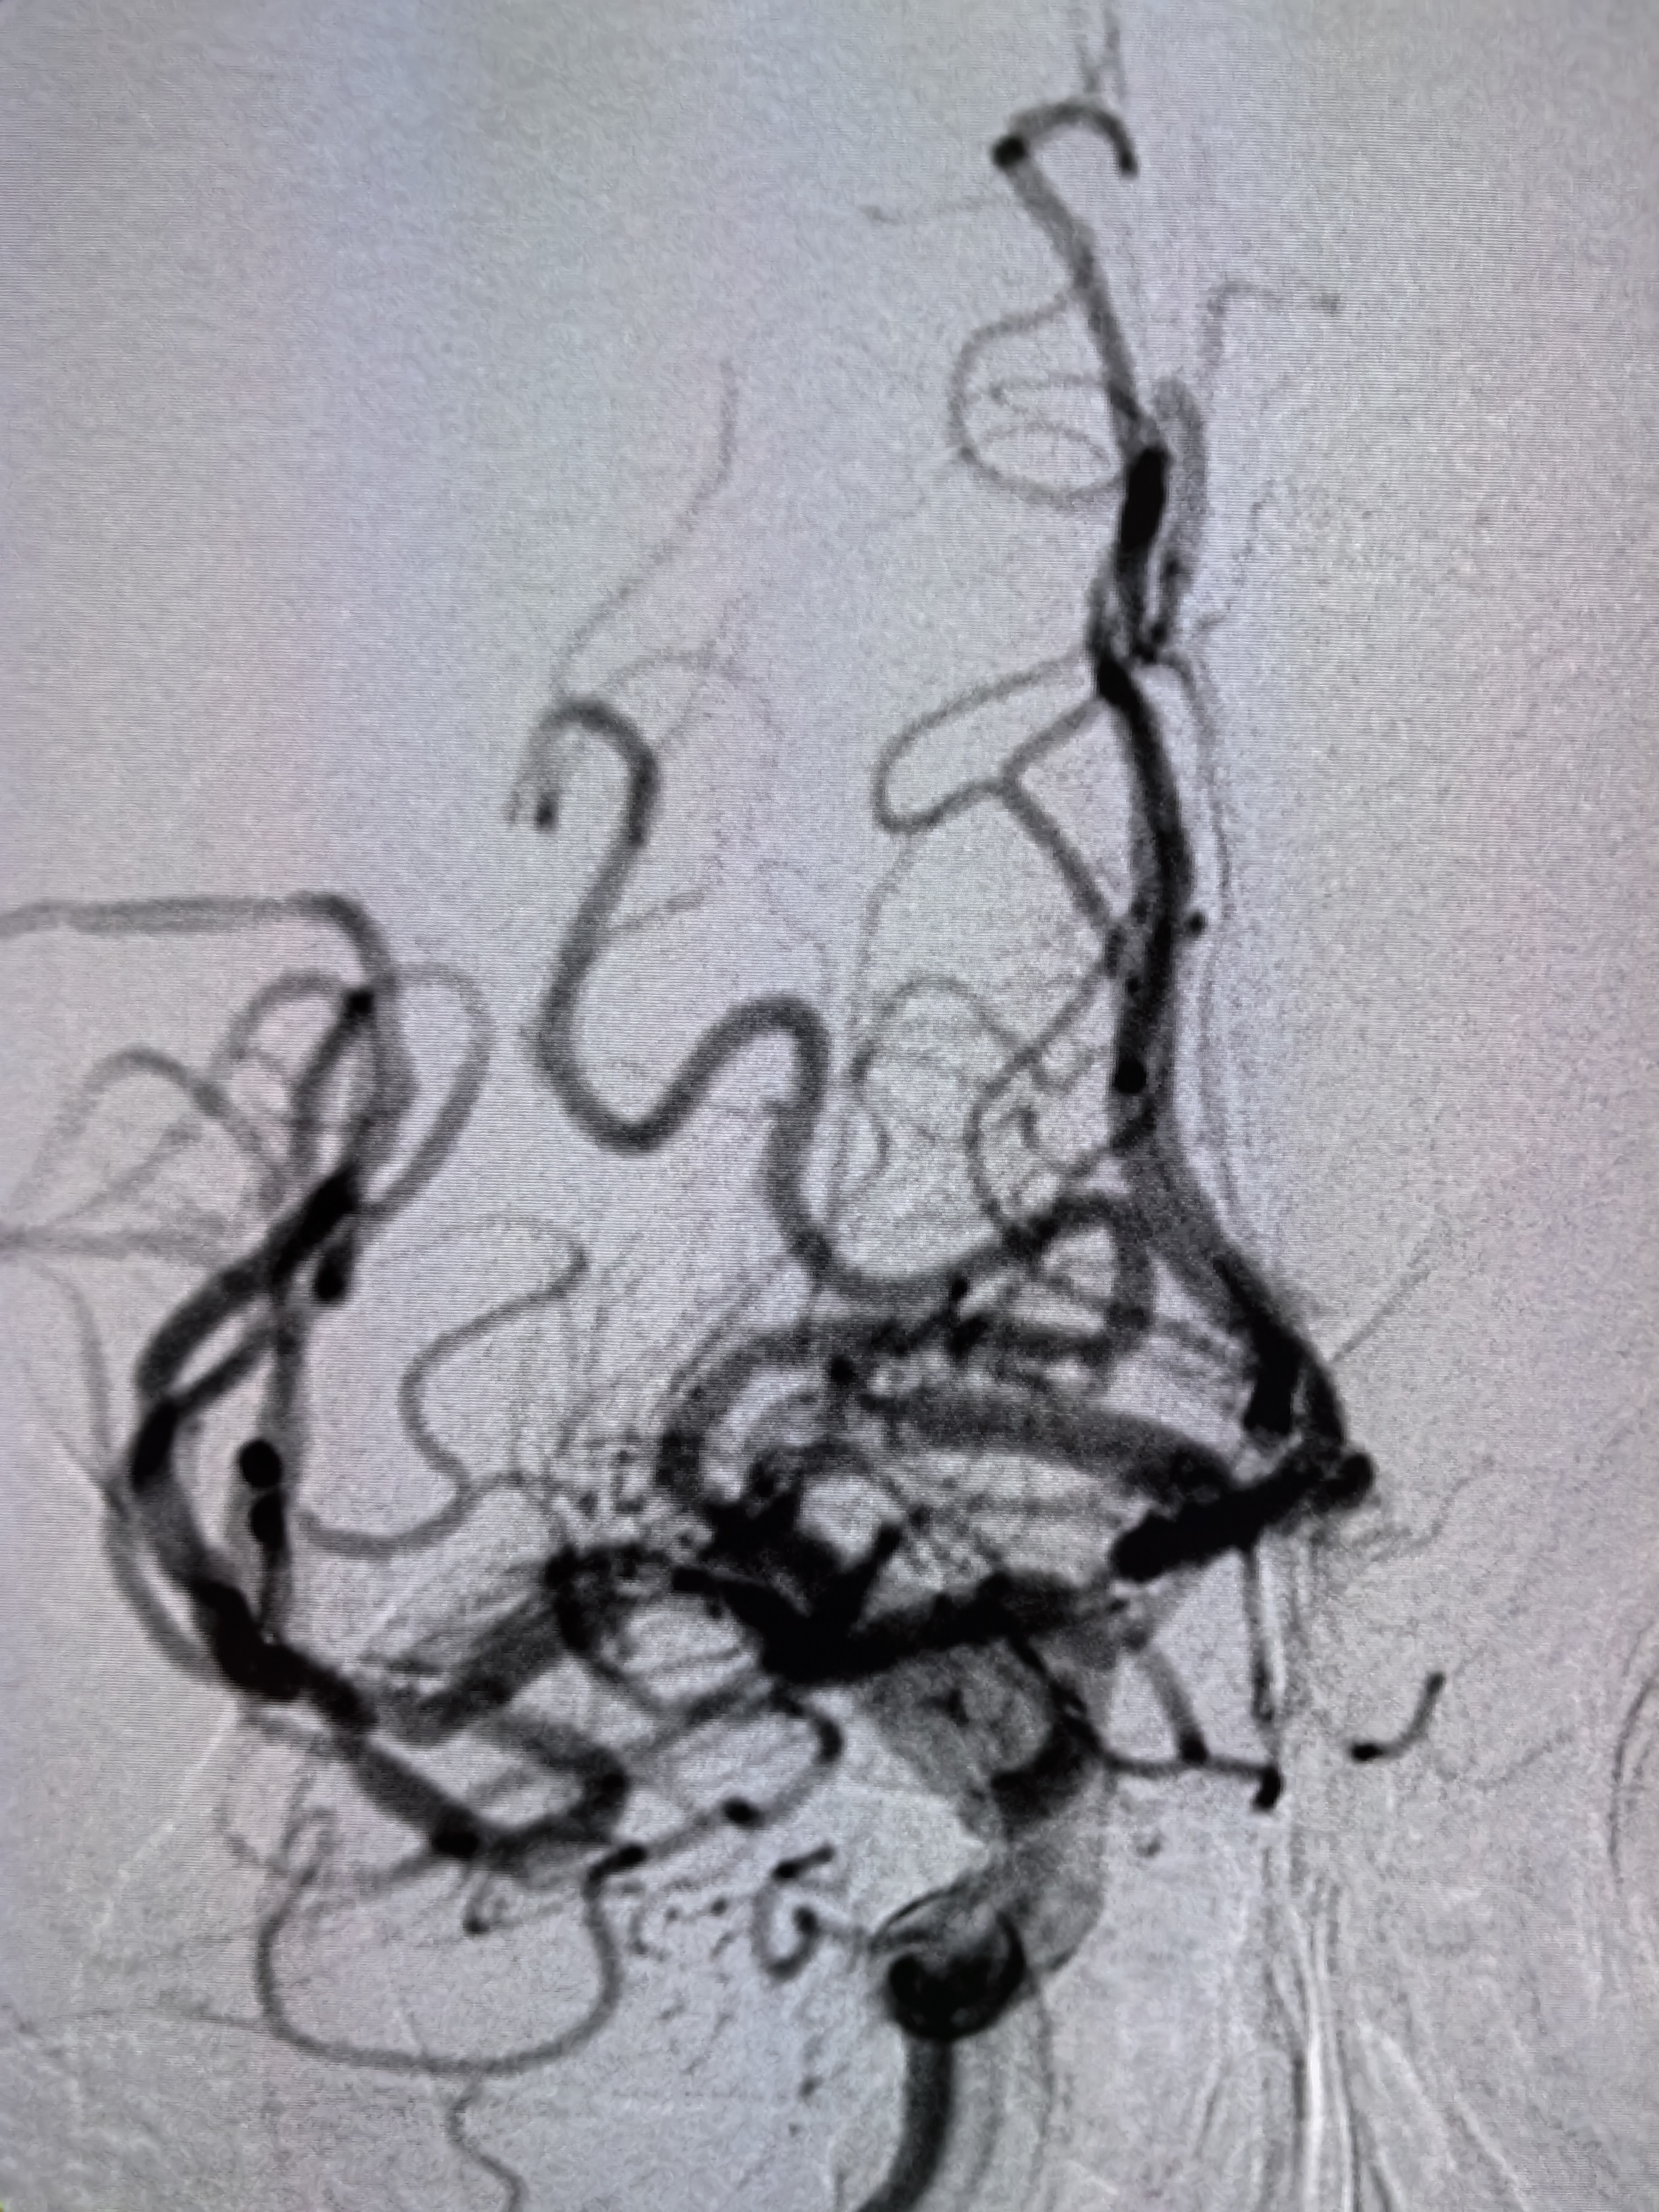

患者ZDY,男性,85岁,突发意识障碍,左侧肢体活动不灵5小时入院。既往房颤,胸腔积液,脑梗死病史多年。患者缘于5小时前突发意识障碍,伴左侧肢体活动不灵,家属发现以后急诊送入院。查体:血压140/90mmHg,房颤节律。浅昏迷,双眼向右侧凝视,余颅神经查体不配合。左侧肢体肌力0级,右侧肌力5级,左侧病理征(+)。NIHSS评分12分。

1、本例患者高龄男性,既往房颤病史,突发意识障碍伴左侧肢体无力,符合大血管病变,具备介入治疗指征。

2、患者高龄,3型弓,颅内血管迂曲,颈内动脉末端闭塞,血栓符合较大,SWIM技术完成取栓。